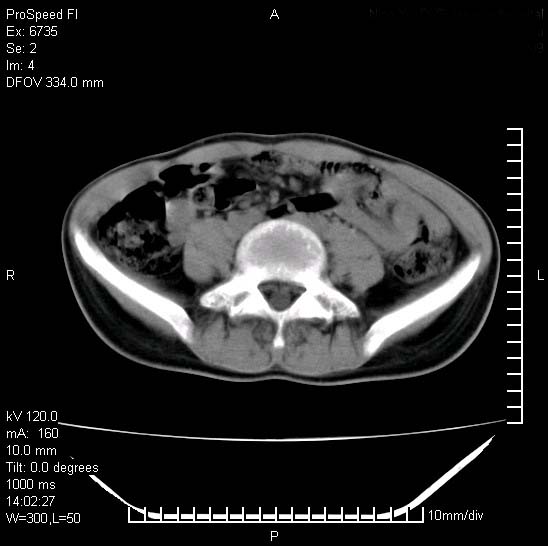

患者自诉胯部疼痛两年余,在当地服用中药,半月前至本院考虑骶髂关节结核,给予抗痨治疗。现发展至右下肢疼痛明显,活动受限,以膝关节处明显,拍膝关节平片无明显异常。

两侧骶骼关节改变,考虑强直性脊炎

右侧骶髂关节也有类似改变,只是较左侧轻,首先考虑强直性脊柱炎,不除外结核,建议作hla-b27检查。

符合强直性脊柱炎表现。